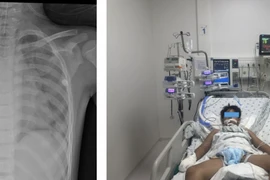

Như trường hợp của người bệnh P.T.N. 62 tuổi (Mạo Khê, Đông Triều) có các triệu chứng tưởng chừng rất “thường gặp” như mệt mỏi, chóng mặt do thiếu máu. Khi bệnh nhân tới bệnh viện và làm các xét nghiệm chuyên sâu để tìm nguyên nhân gây thiếu máu thì được phát hiện ra bệnh ung thư dạ dày.

Với chẩn đoán Ung thư dạ dày giai đoạn 3, người bệnh được tiến hành phẫu thuật cắt toàn bộ dạ dày, nạo vét hạch và điều trị hóa trị theo chỉ định.

Hiện tại sau hơn 6 tháng điều trị theo phác đồ với 8 lần truyền hóa chất, sức khỏe người bệnh hiện ổn định.

thieu-mau-ung-th.jpg

Nội soi phát hiện ung thư dạ dày ở bệnh nhân thiếu máu - Ảnh BVCC